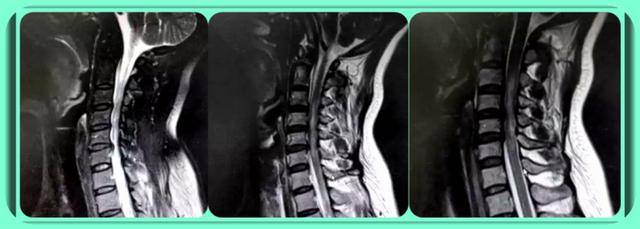

颈椎狭窄,颈椎管狭窄

郑玉堂主任医师接诊后深感吃惊,因为许先生的颈椎重度椎管狭窄,脊髓

颈椎管狭窄都有哪些症状?

引起颈椎椎管狭窄的常见原因有哪些?

颈椎管狭窄了,该怎么办?

但当骨化块增厚增宽到一定程度引起颈椎椎管狭窄时,或是病变进程较快